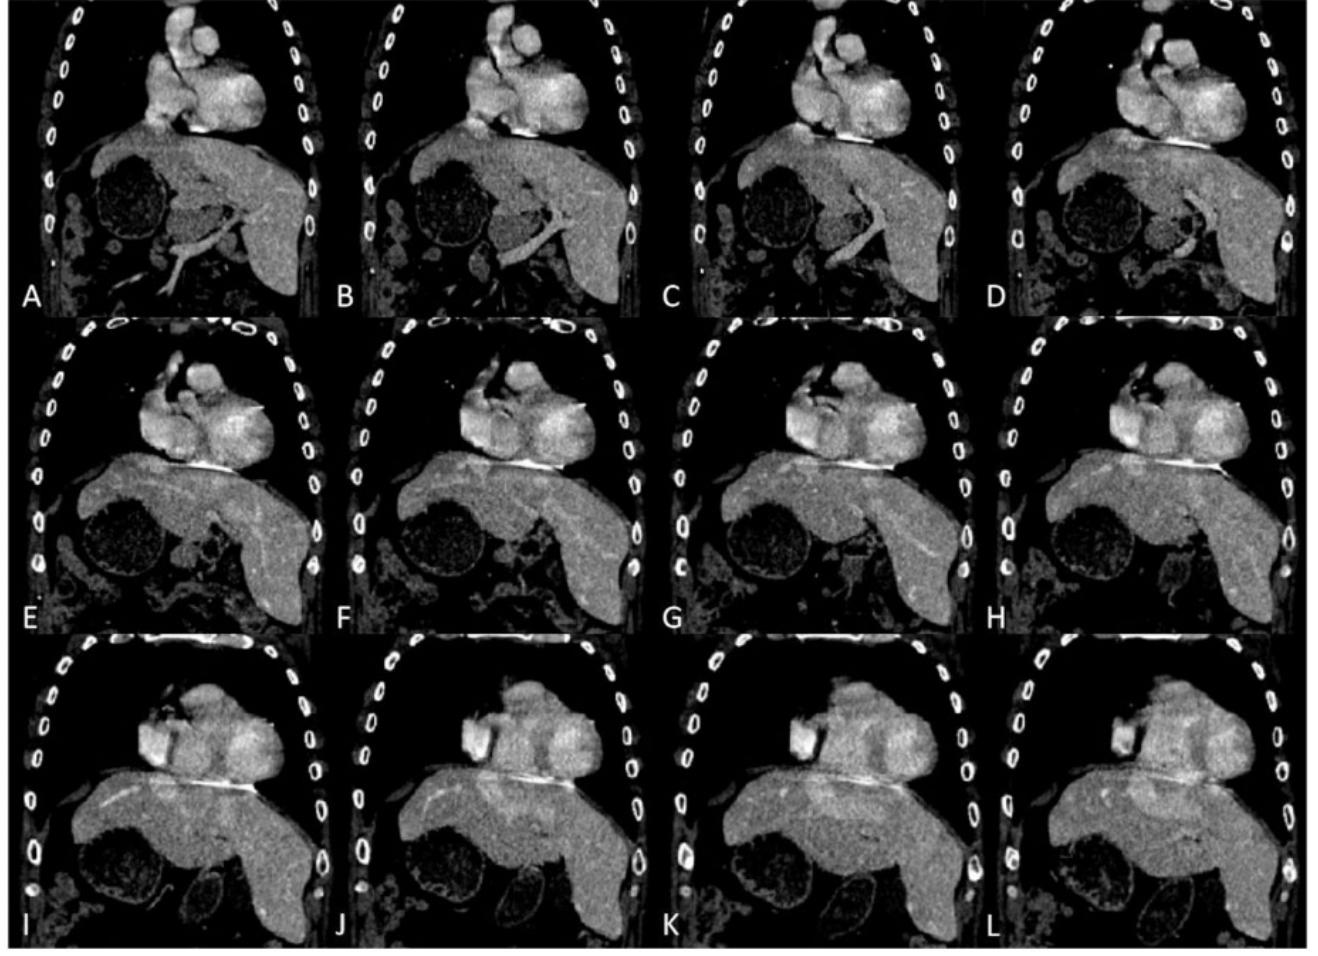

经食管超声心动图证实导丝位置正确,心脏解剖正常,同时发现下腔静脉(IVC)不典型地进入右心房(RA)。在冠状静脉窦(CS)内放置一个可操纵的诊断导管是不可能的,并且这个过程最终被中止。粗略的腹部超声检查显示上腹部器官的方向不典型,没有任何已知的解剖学或先天性异常的既往史。 随后的胸部和腹部计算机断层扫描显示腹部位置反转并伴有左心室颤动。胸部解剖正常;然而,下腔静脉表现出不寻常的过程。它从左侧开始,穿过左侧肝脏,越过右侧与右心房相连(图1)。

图1: 计算机断层扫描图像(A–L)描绘了下腔静脉从停止进入右心房到通过左侧肝脏向左侧更远端的过程。